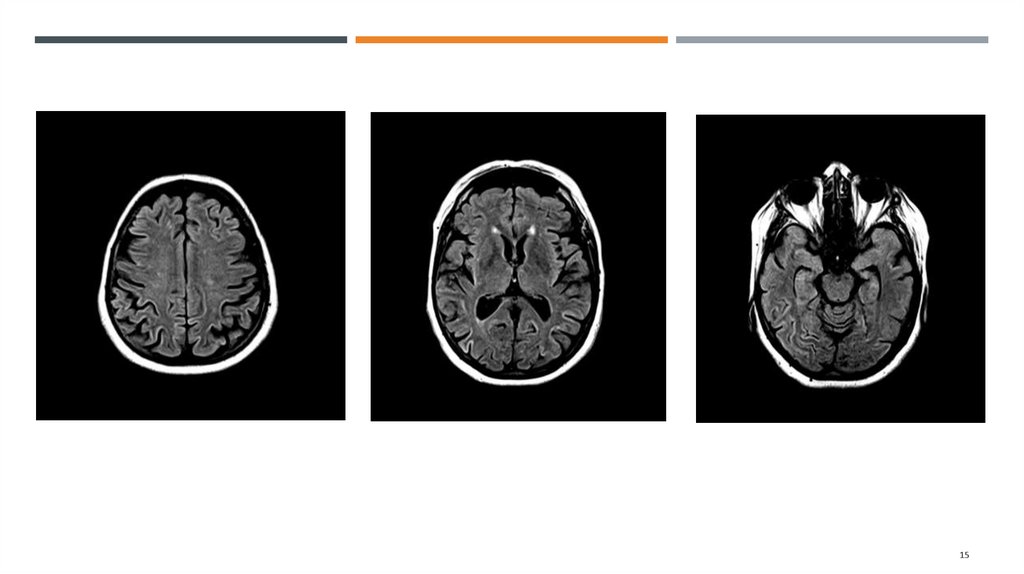

Выявляются множественные асимметричные зоны повышения МР-сигнала на DWI и FLAIR ИП с

вовлечением коры теменных (преимущественно), лобных, затылочных и височных долей (D>S).

В субкортикальных отделах белого вещества лобных и теменных долей выявляются

множественные очаги гиперинтенсивного МР-сигнала на Т2 ВИ и FLAIR ИП размером до 5мм

Заключение:

МР-признаки поражения коры больших полушарий головного мозга. Учитывая анамнез, в

первую очередь необходимо дифференцировать с болезнью Крейтцфельдта-Якоба; в

диф.ряду метаболические (печеночная энцефалопатия), гипоксические изменения маловероятно.

Множественные сосудистые очаги в белом веществе полушарий головного мозга. Расширение

наружных и внутренних ликворных пространств.